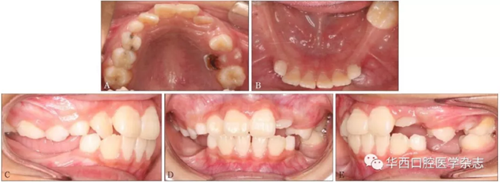

患者,男,10歲,2016年7月因右后牙未萌求治。無正畸治療史、拔牙史、全身系統(tǒng)疾病史,家族成員中無類似畸形?;颊咧委熐翱趦认褚妶D1。

A:上頜面像;B:下頜面像;C:右側像;D:正面像;E:左側像。

圖 1 治療前口內像

臨床檢查:混合牙列,左側磨牙中性關系,前牙淺覆、淺覆蓋,右側側切牙反,下頜恒切牙及左下頜第一磨牙正常萌出,雙側下頜乳尖牙尚未脫落,下頜其余牙齒未見,黏膜色澤正常(圖1)。